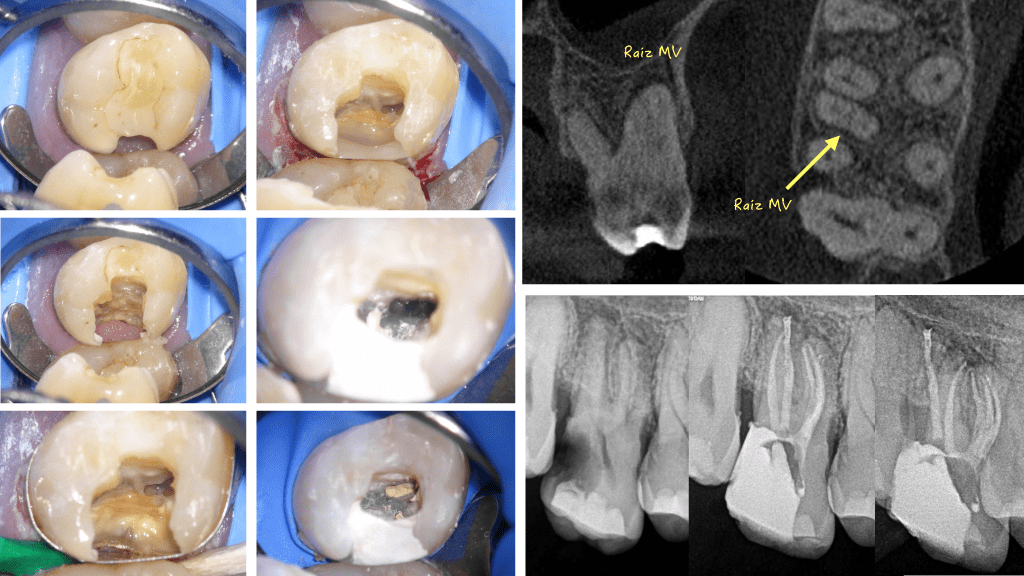

Empiezo una página Facebook nueva (https://www.facebook.com/endodonciabadajoz), con un caso , a mi gusto precioso, lo que para mi es la endodoncia actual , donde necesitamos tener tecnología y conocimientos sumados a un poco de «maña»…. Se trata de un 3.6 con una anatomía que hemos visto muchas veces y que pensamos y esperamos que nunca nos toque:

Cada vez somos más conscientes de la dificultad anatómica de los molares inferiores . Con la ayuda de las microtomógrafías dentales de compañeros en estudios in vitro, que nos hacen ver la complejidad de la raíz mesial, podemos darle la explicación y entender la necesidad el manejo del abordaje quirúrgico para tratar esas piezas.

De este caso que os muestro, he aprendido varias cosas, primera y muy importante, es que el PODER DEL IRRIGANTE solo actuar en aquellas zonas donde la preparación mecánica le ha dejado entrar, por lo que la gran importancia de eliminar mecánicamente tejido o detritus para que el irrigante pueda hacer su trabajo no se debe olvidar.

Y segundo, y quizás más importante , y que muchas veces olvidamos, es que por vía ortógrada, el tratamiento de endodocia , EN OCASIONES, tiene un límite, para unos uno y para otros otro, pero ÉXISTE. Por lo que necesitamos COMPLEMENTAR el tratamiento por vía retrógrada para manejar el caso.